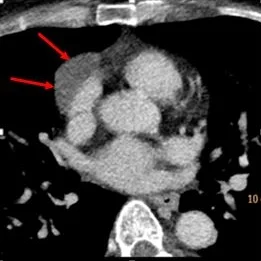

81 year old female with chest pain. Routine CT demonstrates a mediastinal mass that is indeterminate on attenuation measurement. Biopsy is requested.

Conventional CT: Anterior mediastinal "mass".